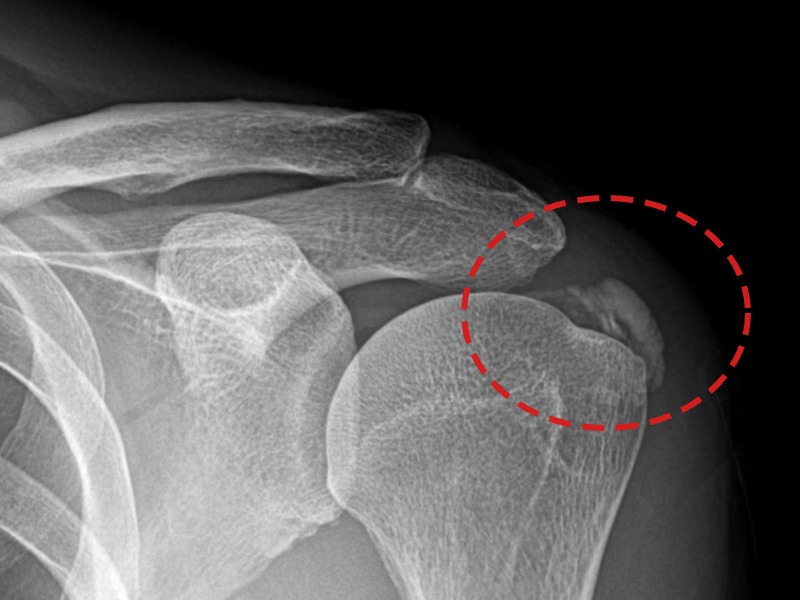

[촬영시기:21.08.30~21.09.09]

[석회분쇄흡입술] 우측 어깨 통증으로 밤잠을 못 이루고 팔을 올리기 어려워진 30대 여성 환자로, X-ray에서 우측 극상근건 내 석회 침착이 확인되어 석회분쇄흡입술을 시행하였습니다.